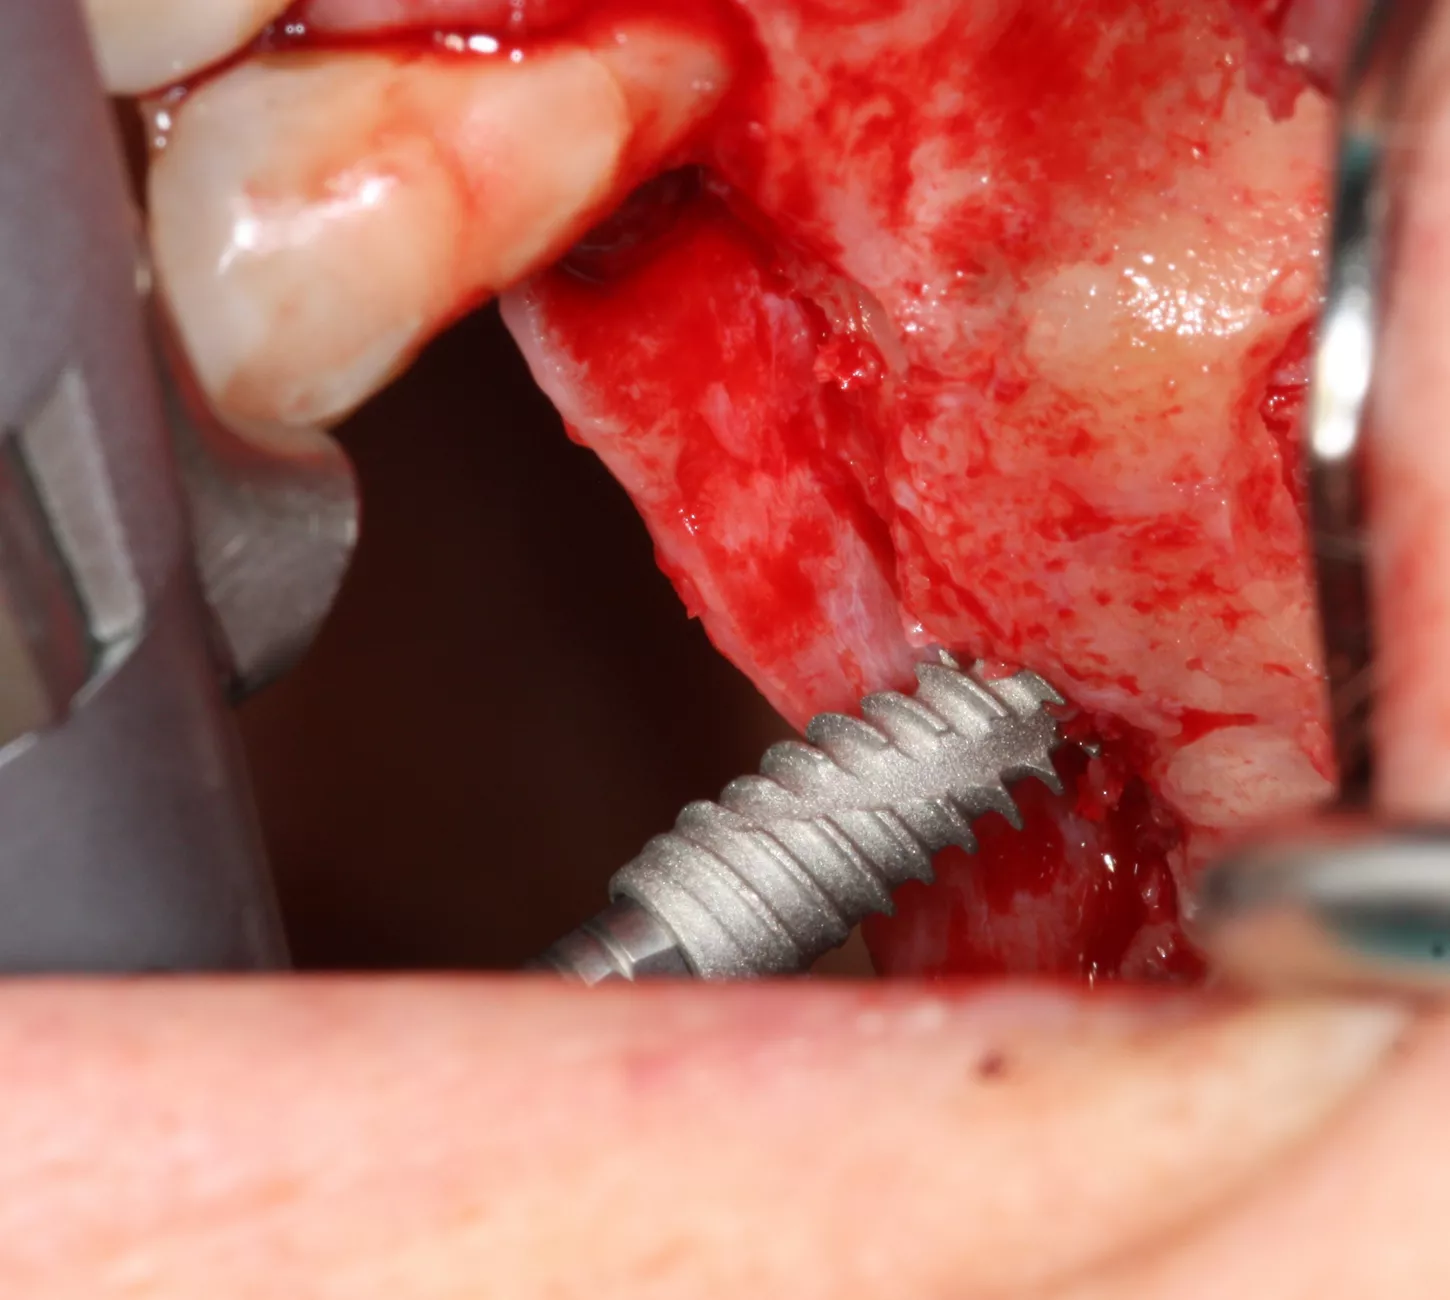

9-10-11. The patient had D3 bone density. Hence an undersized drilling protocol was employed, the final drill diameter being one less than that of the implant. The green drill was used for the 25 implant (diameter 3.4) and the red one for the 26 (diameter 4.0).

9

10

11